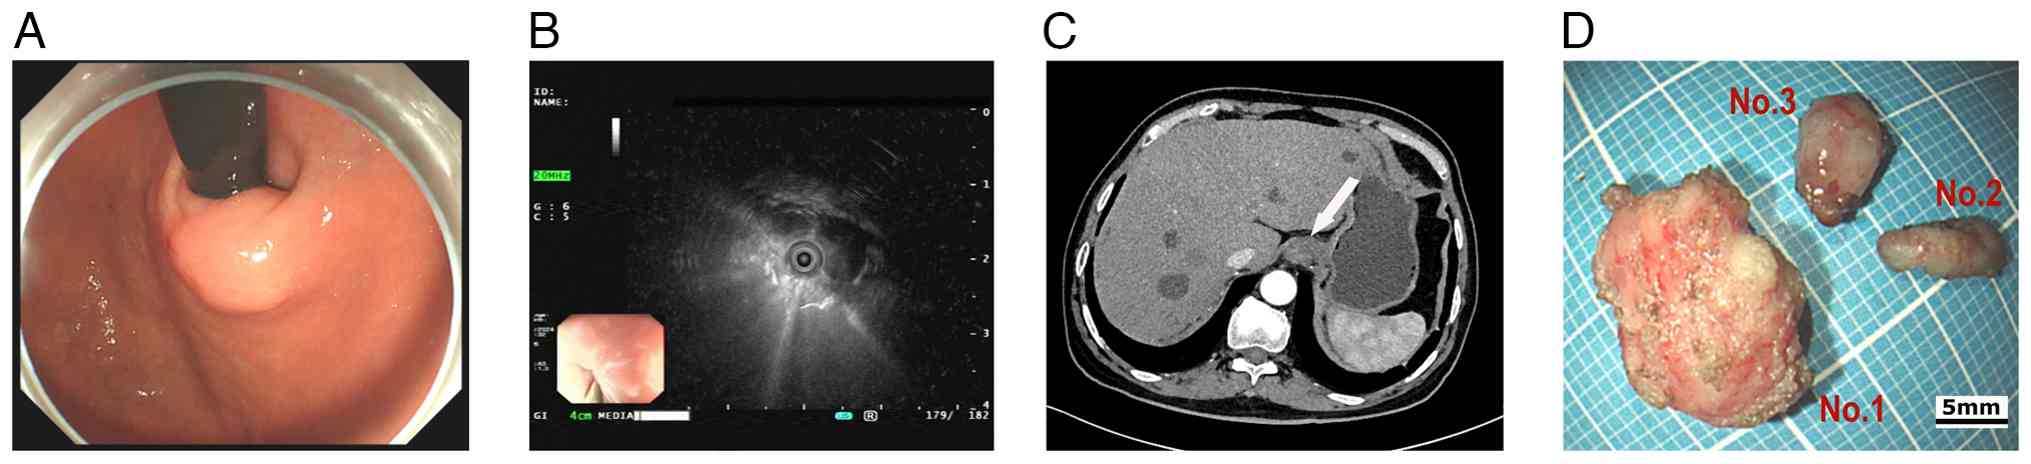

A 72-year-old male patient with a history of type 2 diabetes, hypertension, acute pancreatitis and a pancreatic pseudocyst underwent a gastroscopy examination at Sichuan Science City Hospital (Mianyang, China) without presenting with any symptoms during a physical examination in June 2024. Physical examination showed mild upper abdominal tenderness, and the psychosocial and family medical histories of the patient were unremarkable. Gastroscopy identified chronic gastritis and a 15-mm SEL in the cardia (Fig. 1A); consequently, endoscopic ultrasonography (EUS) revealed the lesion originated from the muscularis propria, appearing as a heterogeneous hypoechoic mass with internal septa, which measured 13.9x9.2 mm (Fig. 1B). The CT scan showed a slightly thickened 15-mm nodule in the cardia with slight homogeneous enhancement and no signs of infiltration or metastasis (Fig. 1C).

Clinical examination results and

postoperative specimens. (A) Gastroscopy showed a subepithelial

lesion at the cardia of the stomach. (B) Endoscopic ultrasonography

described a heterogeneous hypoechoic mass with internal septa. (C)

CT scan revealed slight homogeneous enhancement in arterial phase,

no metastasis (the white arrow indicates the tumor). (D) After the

operation, three solid tumors were obtained-gross appearance of

tumors no. 1, 2 and 3 (scale bar, 5 mm).

Figure 1

Clinical examination results and postoperative specimens. (A) Gastroscopy showed a subepithelial lesion at the cardia of the stomach. (B) Endoscopic ultrasonography described a heterogeneous hypoechoic mass with internal septa. (C) CT scan revealed slight homogeneous enhancement in arterial phase, no metastasis (the white arrow indicates the tumor). (D) After the operation, three solid tumors were obtained-gross appearance of tumors no. 1, 2 and 3 (scale bar, 5 mm).